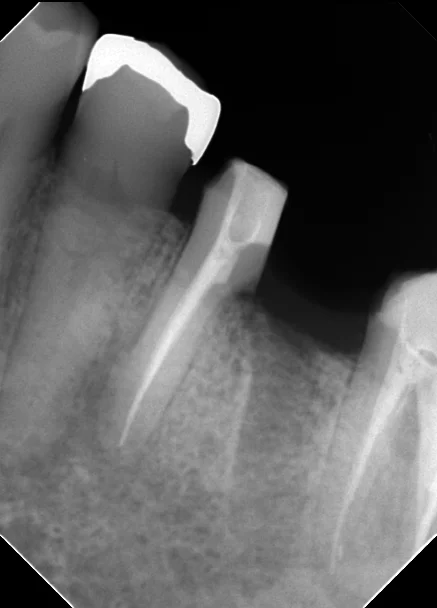

なので、こんな感じで一本だけ抜歯すれば、手前の根は残すことが出来るようになります。

残した方の歯の神経の治療を行うかどうかは先生の考えかたに寄るかもしれませんが・・・

私は確実に感染が生じていると思っていますので、必ず根管治療を行います。

拡大視野ではなく、裸眼で治療された場合は根の管を見逃していることが結構ありますので、再根管治療しておかないと予後が不安なんですよね・・・。

今回の場合も2本の根の管があるように最初のレントゲン上では写っていましたが、実際にはその2本は非常に細い道でつながっており、しかも元々の根の管がその細い道の中に隠れていました。

最初のレントゲンに比べると神経の治療後の薬が根の先まで綺麗に入っているのが分かるかと思います。

無事に神経の治療も終わり、後ろの根の抜歯後の傷も問題なく治ったため、最終的な被せ物に移行することとなりました。